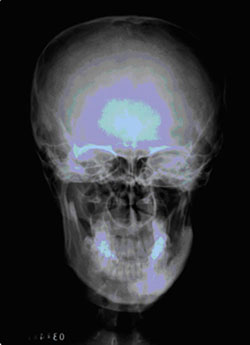

眶颧部的骨质缺损会使得上面部明显凹陷,严重影响外观。以下就是一幅额颞部缺损的正面照片。

图4 左侧额颞部颅骨缺损的正面观

(图片来自Journal of craniomaxillofacial surgery)